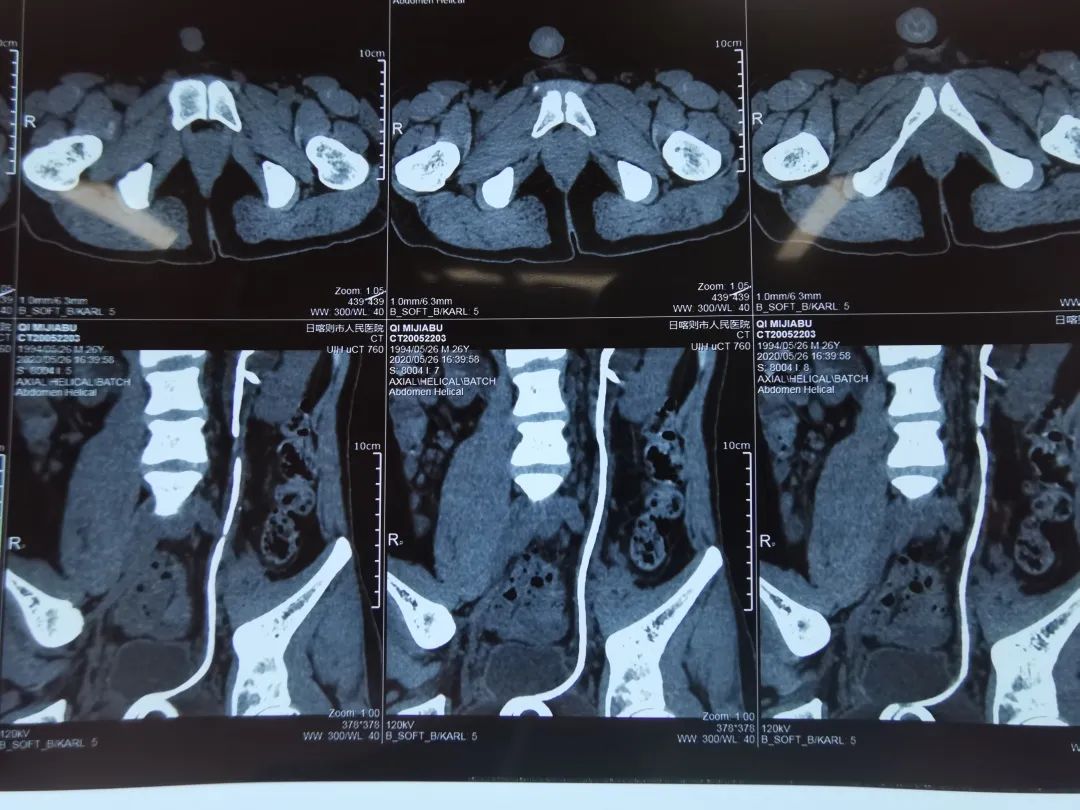

日喀则市人民医院泌尿外科成功施救复杂性尿路结石患者

值得注意的是,本次手术一改传统的开放手术方式,综合运用了输尿管硬镜、软镜及微通道经皮肾镜等所有上尿路结石治疗的微创手段,使患者避免了开放手术所造成的伤害。目前,在上海援藏医疗队的帮助下,日喀则市人民医院已能够常规开展经皮肾镜取石术治疗肾结石、输尿管镜下钬激光碎石术治疗输尿管结石,这是医院推进西藏(西部)泌尿外科疾病诊治中心建设的重要一步,也标志着日喀则地区微创化治疗上尿路结石等复杂性尿路结石症技术的稳步发展。